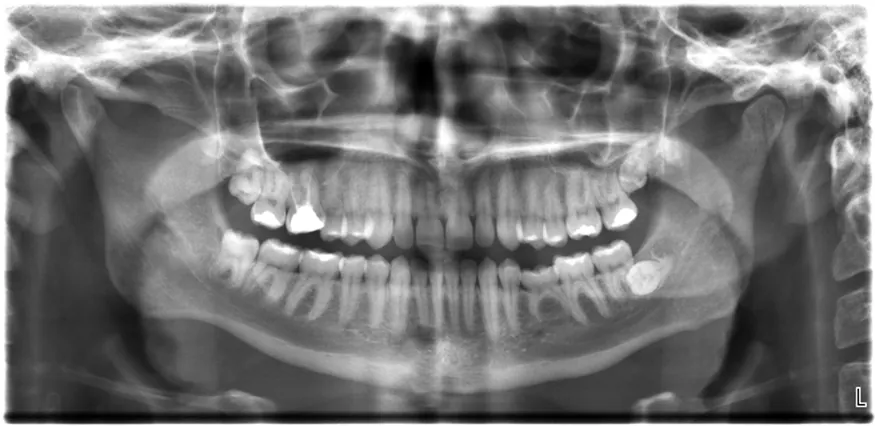

All of us can identify diagnostic uses of x-ray photons. Among these are the universal dental and medical x rays that have become an essential part of medical diagnostics. (See Figure 30.23 and Figure 30.24.) X rays are also used to inspect our luggage at airports, as shown in Figure 30.22, and for early detection of cracks in crucial aircraft components. An x ray is not only a noun meaning high-energy photon, it also is an image produced by x rays, and it has been made into a familiar verb—to be x-rayed.

The X-ray image of front view of the jaw, especially the teeth.

Figure 30.22 An x-ray image reveals fillings in a person’s teeth. (credit: Dmitry G, Wikimedia Commons)